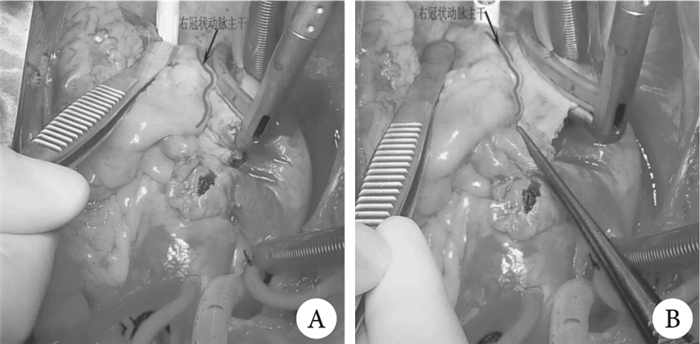

注:A為本例消融操作;B為正確消融操作

入院后予以吸氧,利尿,擴管,營養心肌,低分子肝素抗凝等治療。積極術前準備后,經前正中切口在全身麻醉低溫體外循環下行二尖瓣和主動脈瓣機械瓣置換、三尖瓣成形及改良迷宮雙極射頻消融術。術中探查見:左、右心房增大,左、右冠狀動脈(左、右冠)分支未捫及確切硬化斑塊,心肌收縮有力;主動脈瓣呈三瓣,瓣葉增厚,呈結節狀改變,部分鈣化,交界粘連,開口呈中度狹窄伴中度關閉不全狀;三尖瓣環擴大,可容納三指半,瓣葉無增厚、卷曲,試水呈中度關閉不全;二尖瓣葉明顯增厚、卷曲,交界粘連,開口中度狹窄,瓣下腱索增粗,部分融合。術中于升主動脈遠端插動脈灌注管,上腔靜脈直角插管,右心房近下腔靜脈匯入處插下腔靜脈引流管,建立體外循環,并行循環,先不降溫,分別阻斷上、下腔靜脈,縱行切開右心房壁,心臟跳動下予以AtricureTM雙極射頻消融鉗完成右心房切口至右心耳、右心房切口至下腔靜脈(圖 1)、右心房切口至右房室溝徑線消融;降溫至鼻咽溫32 ℃,阻斷升主動脈,縱行切開升主動脈,經左、右冠開口予以HTK液灌注心臟;電刀切斷Marshall韌帶;左心房近房間溝處切開,同時距離左心耳根部5 mm處切除左心耳,予以消融鉗完成左、右肺靜脈環、右上肺靜脈至左上肺靜脈、右下肺靜脈至左下肺靜脈、左心耳至左上肺靜脈、左心耳至左下肺靜脈、左小房近房間溝切口下份至二尖瓣瓣環、冠狀靜脈竇至房間隔徑線消融,5-0 Prolene縫線連續雙層縫合左心耳切口;切除病變二尖瓣膜,保留部分后瓣及瓣下結構,測瓣能順利通過29號測瓣器,取ONXMC-25/33號機械瓣予以換瓣線間斷縫合置換二尖瓣,落位滿意,試瓣啟閉良好,3-0 Prolene縫線連續雙層縫合關閉房間隔和左心房近房間溝處切口(跨過二尖瓣機械瓣口留置左心室引流管);切除病變主動脈瓣膜,測瓣能順利通過21號測瓣器,取ONXAC-21號機械瓣予以換瓣線間斷縫合置換主動脈瓣,落位滿意,試瓣啟閉良好,左、右冠狀動脈開口無影響,4-0 Prolene縫線連續雙層縫合關閉升主動脈切口;予以3-0 Prolene縫線環縮三尖瓣前、后瓣環行三尖瓣De Vega成形術,試水見瓣膜閉合滿意;復溫,左心充分排氣后松開升主動脈阻斷鉗,心臟自動復跳,5-0 Prolene縫線連續雙層縫合關閉右心房壁切口;輔助循環滿意后,試停并行循環,但患者血壓下降,右心室收縮力差,加量多巴胺至10 μg?kg-1 ?min-1,腎上腺素至0.1 μg?kg-1 ?min-1,血壓僅維持在60/40 mm Hg左右,右心室收縮力無改善;再次并行循環,輔助30 min后,心率80~100次/分(心電監護提示竇性心律),試停機,血壓亦只能維持在60/40 mm Hg左右,右心室收縮力仍差;經左心引流管測壓提示左心房壓力約12 cm H2O;術中捫及肺動脈壓力不高;心電監護顯示ST段抬高;經食管超聲心動圖見二尖瓣位和主動脈瓣位機械瓣膜在位,啟閉良好,未見明顯異常,左、右冠開口可見,三尖瓣收縮期探及微量反流,右心室收縮功能降低,右心室和右心房脹滿,左心室空虛。繼續并行循環,輔助心臟,同時進行平衡超濾。患者右心功能不全,對血管活性藥物不敏感,心電圖示有ST段改變,考慮在行右心房切口至下腔靜脈徑線消融時,因離右冠主干較近,可能損傷右冠主干,導致右冠狹窄,遂取一段左下肢大隱靜脈橋,心臟跳動情況下,暴露右冠主干遠端(位于可疑損傷處以遠),使用米道斯固定器固定右冠主干,用7-0 Prolene縫線將大隱靜脈橋近心端與右冠主干遠端吻合;此時發現心包腔內積血增多,色鮮紅,搬起心臟見左心室后壁近房室溝處有一血腫,大小約4.0 cm×2.0 cm,心外膜有滲血,考慮左心室后壁破裂可能,遂再次降溫,阻斷升主動脈,經升主動脈根部插管予以HTK液灌停心臟,拆開右心房壁、房間隔切口縫線,拆掉二尖瓣機械瓣,發現左心室后壁破裂,裂口位于二尖瓣環6~8點鐘方向平行于瓣環,長約2.5 cm,深約0.3 cm,予以4-0 Prolene縫線帶毛氈片間斷褥氏縫合左心室裂口(從左心室進針,跨過二尖瓣環,從左心房出針),共計3針;重新縫合二尖瓣機械瓣膜;3-0 Prolene縫線連續雙層縫合關閉房間隔切口;升主動脈戳孔,予以6-0 Prolene縫線將大隱靜脈橋遠心端與升主動脈戳孔吻合,再次復溫,左心及橋血管充分排氣后松開升主動脈阻斷鉗,心臟自動復跳,5-0 Prolene縫線連續雙層縫合關閉右心房壁切口;搬起心臟見左心室后壁近房室溝處血腫無增大,心外膜未再滲血;右心室收縮功能較前改善,但血壓仍偏低,加大血管活性藥物劑量后,血壓升高不明顯,遂經右側股動脈插管植入Datascope 40cc球囊反搏導管,進行主動脈內球囊反搏[心率90~110次/分,主動脈內球囊反搏(IABP)反搏比1 : 1],在靜脈泵入多巴胺20 μg?kg-1 ?min-1,腎上腺素0.2 μg?kg-1 ?min-1,去甲腎0.06 μg?kg-1 ?min-1的情況下,血壓維持在100~110/60~80 mm Hg,順利停機。徹底止血后逐層關胸。體外循環時間509 min,升主動脈阻斷時間216 min,手術時間700 min。患者術后入ICU監護,予以抗炎,抑酸,化痰,營養支持,維持水電解質酸堿平衡等治療,同時靜脈泵入血管活性藥物維持循環穩定、可達龍抗心律失常。術后呼吸機輔助呼吸136.67 h,IABP輔助84 h,ICU入住162.17 h。術后并發肺部感染和肝功能異常,經過積極治療,均治愈。術后第14 d經胸超聲心動圖提示二尖瓣位和主動脈瓣位人工機械瓣膜未見明顯異常,左心房增大,左心室飽滿,三尖瓣輕度關閉不全,收縮期三尖瓣上探及Ⅰ級反流;LA 44 mm,右心室內徑(LVD)50 mm,RAD 43 mm×38 mm,右心室內徑(RVD)19 mm,EF 0.65。術后第18 d心電圖提示房顫伴快速心室率,HR102 bpm,T波改變。患者于術后第18 d痊愈出院,心功能恢復至Ⅰ~Ⅱ級,口服華法林2.5 mg qd抗凝,可達龍0.2 bid抗心律失常治療。術后第6個月復查經胸超聲心動圖提示二尖瓣位和主動脈瓣位人工機械瓣膜未見明顯異常,左心房增大,左心室稍大,三尖瓣輕中度關閉不全,收縮期三尖瓣上探及Ⅰ~Ⅱ級反流,反流面積4.3 cm2,LA 44 mm,LV 51 mm,RA 41 mm×38 mm,RV 18 mm,EF 55%;心電圖提示竇性心律,HR 72 bpm,ST-T改變;停服可達龍,僅單服華法林抗凝,凝血酶原時間國際標準化比值(INR)維持在1.8~2.2。術后隨訪11個月,患者無心悸、心累、氣促、胸痛癥狀,心功能恢復至Ⅰ級。

討論????直視雙極射頻消融術是治療風心病合并房顫的有效方法,目前已在臨床廣泛開展,長期竇性維持率高達82.40%~87.01%,并發癥發生率低,術中損傷右冠主干的嚴重并發癥尚未見報道[1-3]。本例患者由于下腔靜脈插管處荷包距離右房室溝較近,可能在消融右心房切口至下腔靜脈徑線時,因消融鉗距離右冠主干較近,熱傳導損傷右冠主干,使右心室肌血供減少,從而導致心臟復跳后右心室收縮力較差,右心血液不能足量進入肺動脈,使得左心血容量不足,導致主動脈血壓降低。另外,此患者為女性,48歲,雖無“三高”病史,但術前心電圖提示ST-T改變,亦是冠心病高危人群,術中心臟復跳后右心功能差,也可能系術前合并右冠病變,術前最好行冠脈造影檢查,除外冠心病,以便于術中判斷。